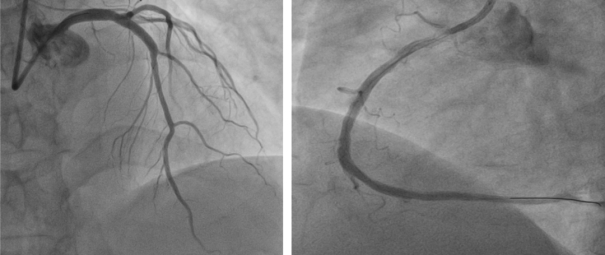

不稳定型心绞痛属于急性冠脉综合征范畴,大多因冠脉粥样硬化斑块破裂、血栓形成,导致冠脉部分或完全阻塞,从而引发心肌缺血,严重者甚至进展为心肌梗死。同时,考虑冠脉CTA与诊断冠心病的金标准冠状动脉造影(冠脉造影)相比,准确程度稍差,诊断特殊病变受限。在充分与家属沟通后,心脏中心李龙虎主任医师为患者安排了冠脉造影。冠脉造影提示,LAD(前降支)近段可疑夹层,RCA中段重度狭窄。

▲ 冠脉造影结果